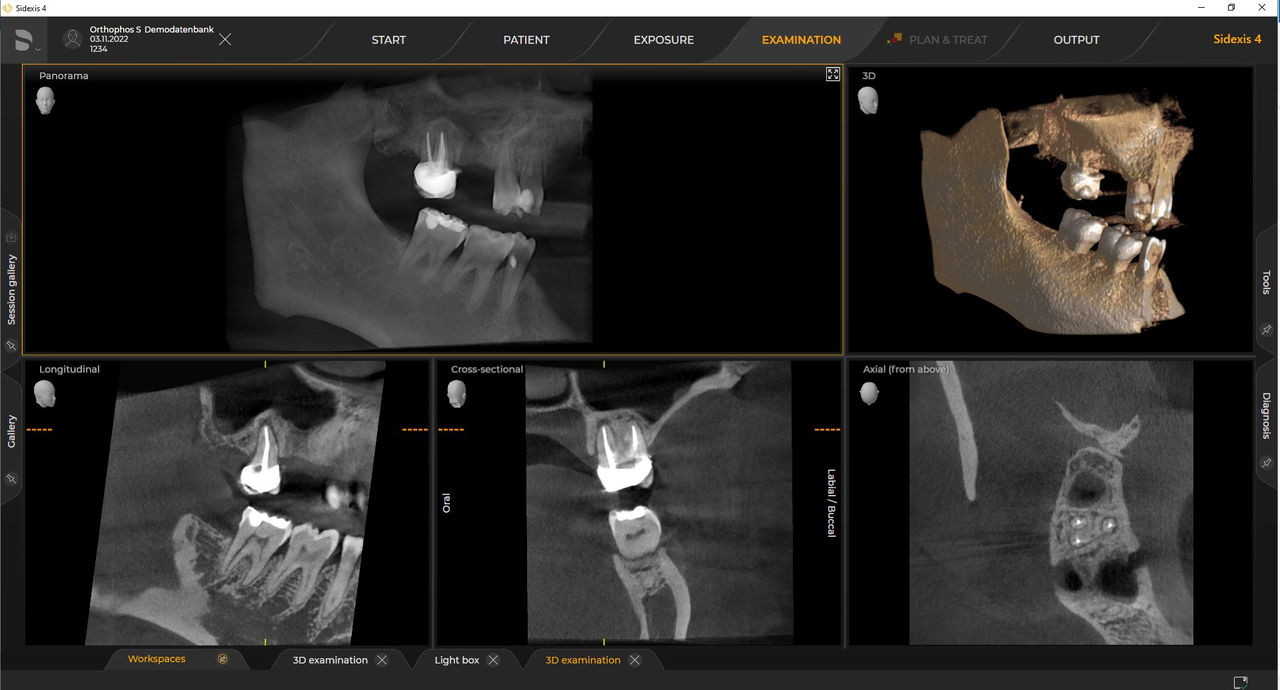

Dzięki Low Dose — trybowi 3D inteligentnej niskiej dawki — można uzyskać obrazy 3D w zakresie dawek promieniowania rentgenowskiego 2D. W trybie HD (do 1400) pojedyncze obrazy są przechwytywane podczas jednej rotacji i konwertowane na objętość 3D o wielkości do 80 μm w celu uzyskania obrazów o niskim poziomie szumów i wysokiej rozdzielczości.

Urządzenia rentgenowskie firmy Dentsply Sirona współpracują wyłącznie z systemem Sidexis 4. Można łatwo przenieść dane z systemu Sidexis XG do systemu Sidexis 4. Sidexis 4 zapewnia pełną funkcjonalność cyfrową dzięki najnowszym narzędziom